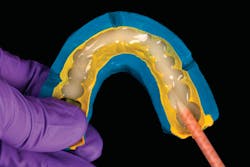

Esthetic functional prototypes have been utilized to test drive the proposed smile design, vertical dimension, phased treatment plan, and functional blueprint for future care.3–5 Different materials and techniques have been used to create bonded functional prototypes, such as polymethyl methacrylate (PMMA) and highly filled flowable composites.6–9

A patient presented with multiple deficient restorations, discolored teeth, and attrition (figures 1–4). The patient’s treatment plan was a full-mouth rehabilitation with a combination of veneers, crowns, and onlays.

Esthetic and functional prototypes are an effective way to evaluate esthetics and function of a proposed restorative plan, all while spreading the cost of definitive treatment over time. Esthetic, functional, and long-lasting restorations can be achieved if clinical and laboratory protocols are carefully followed using adhesive additive techniques.